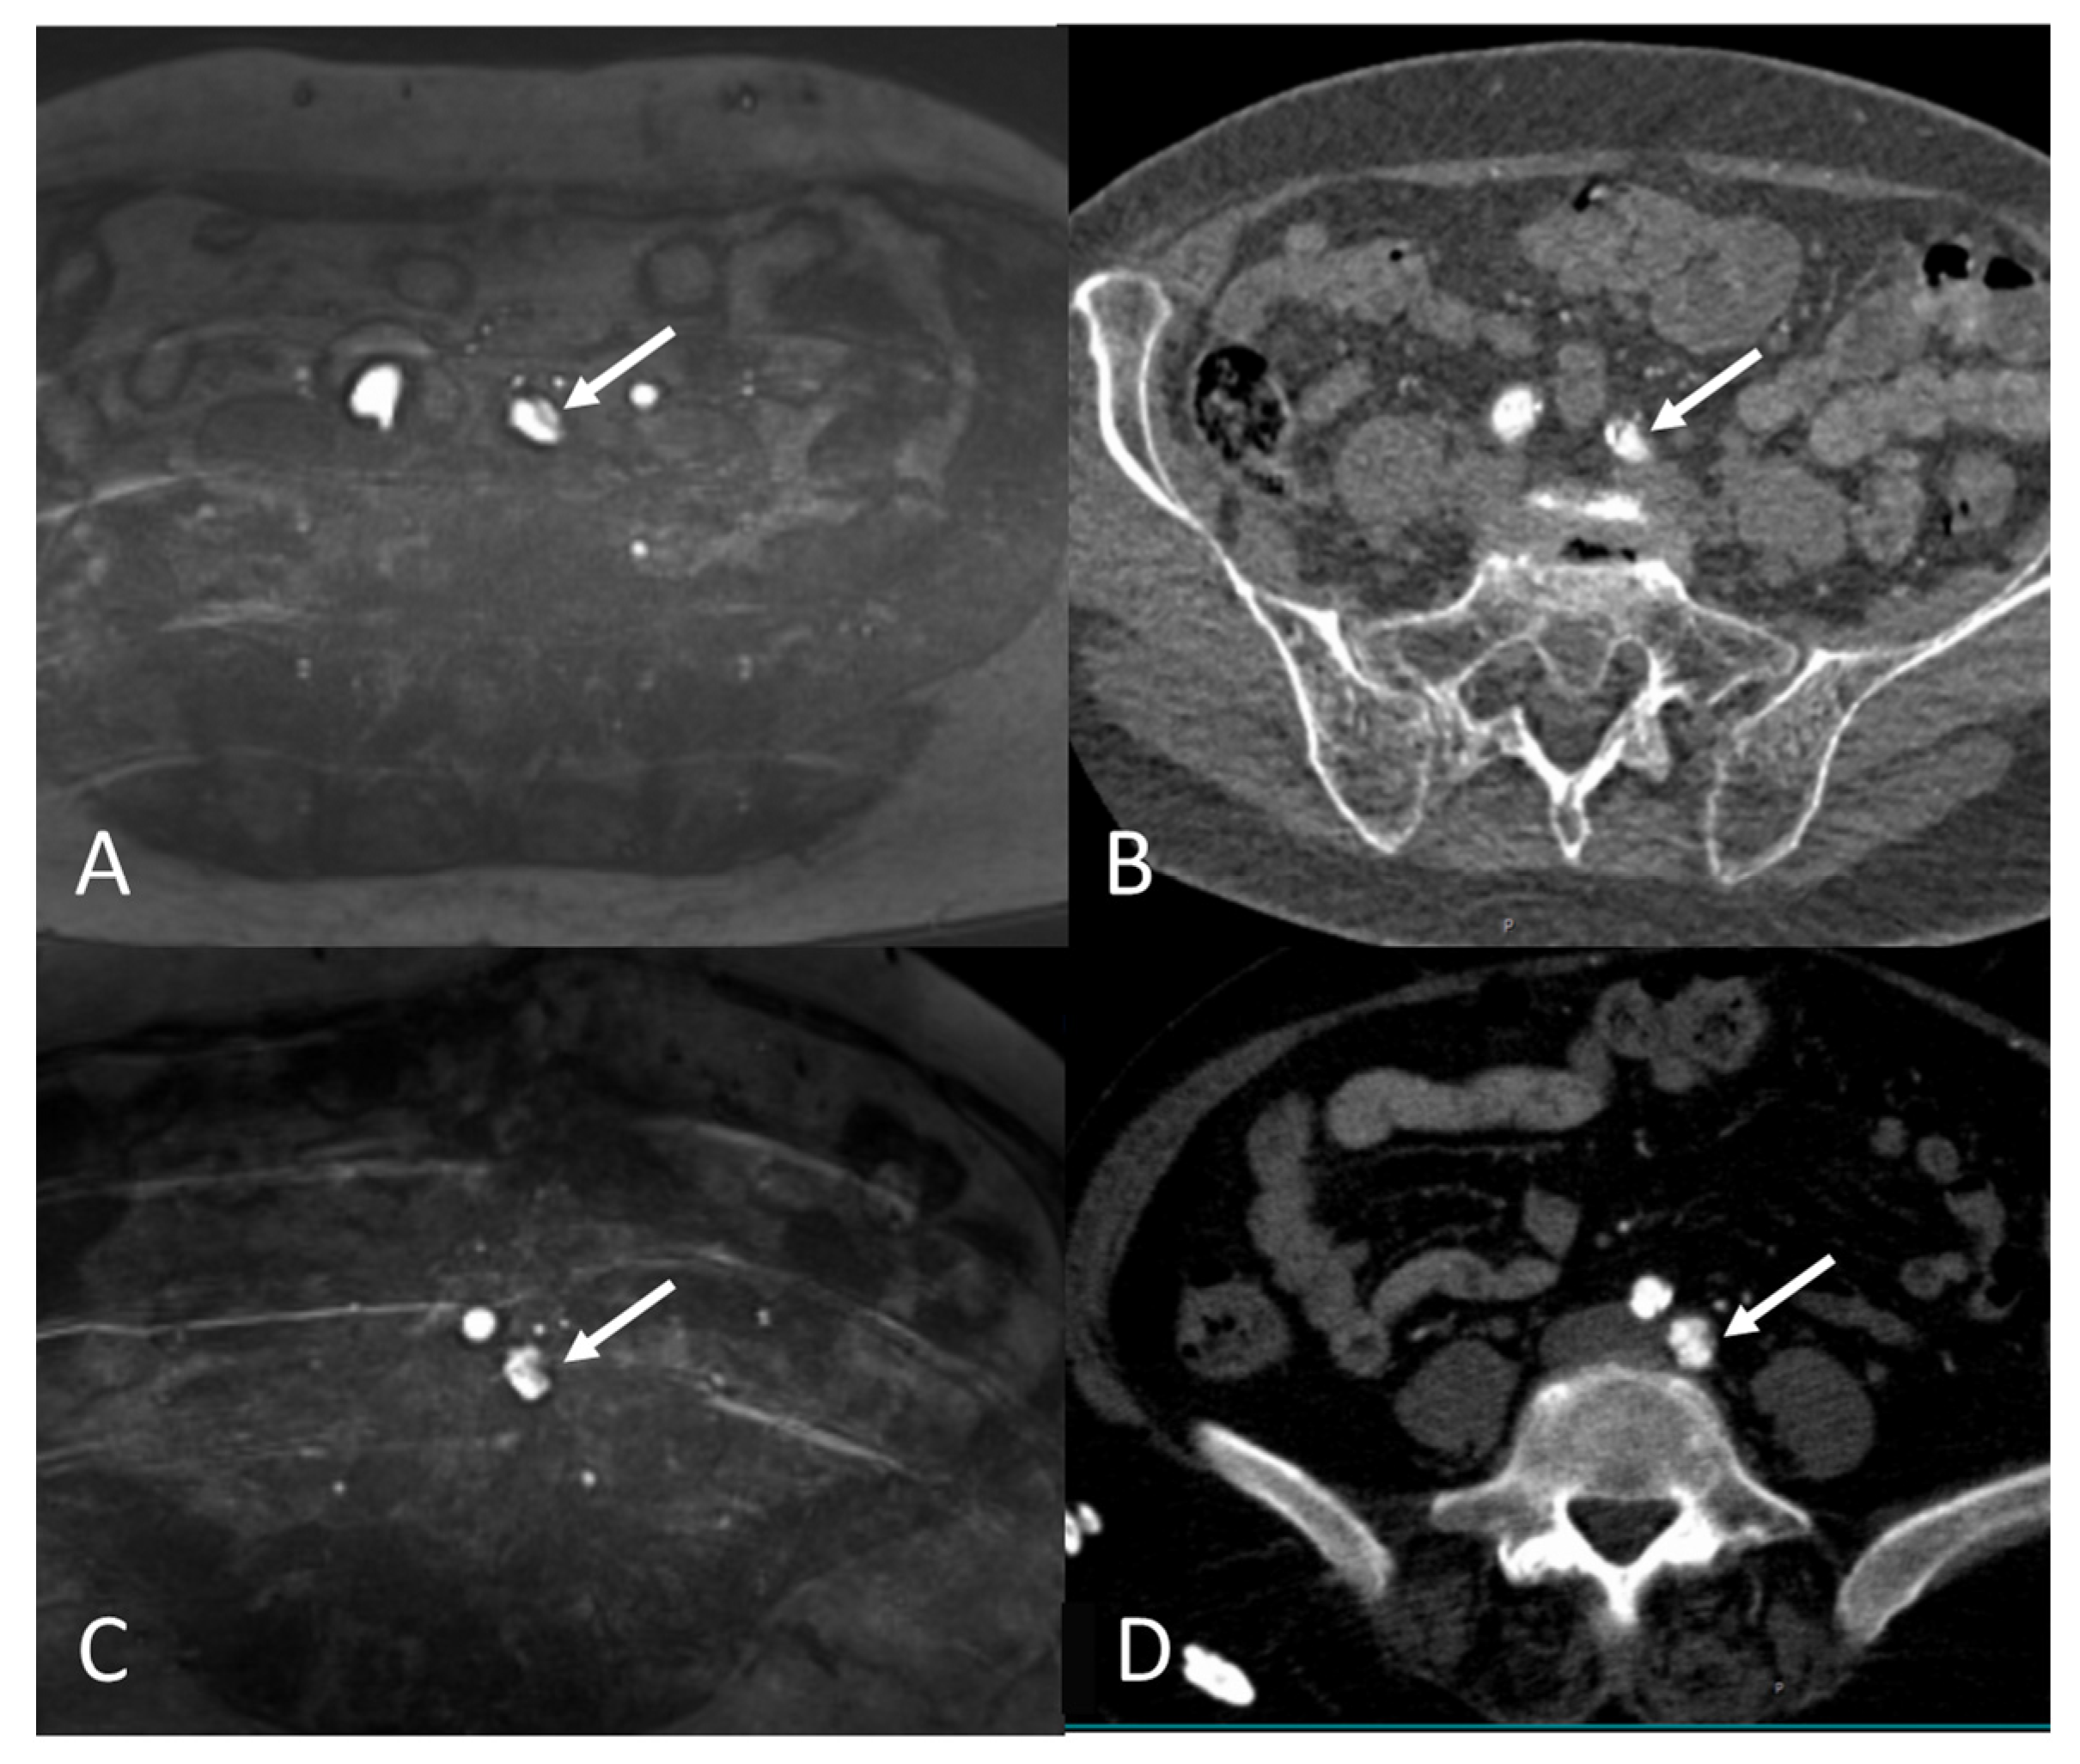

2.4. Image Review Methods

2.5. Assessment of the Access Route